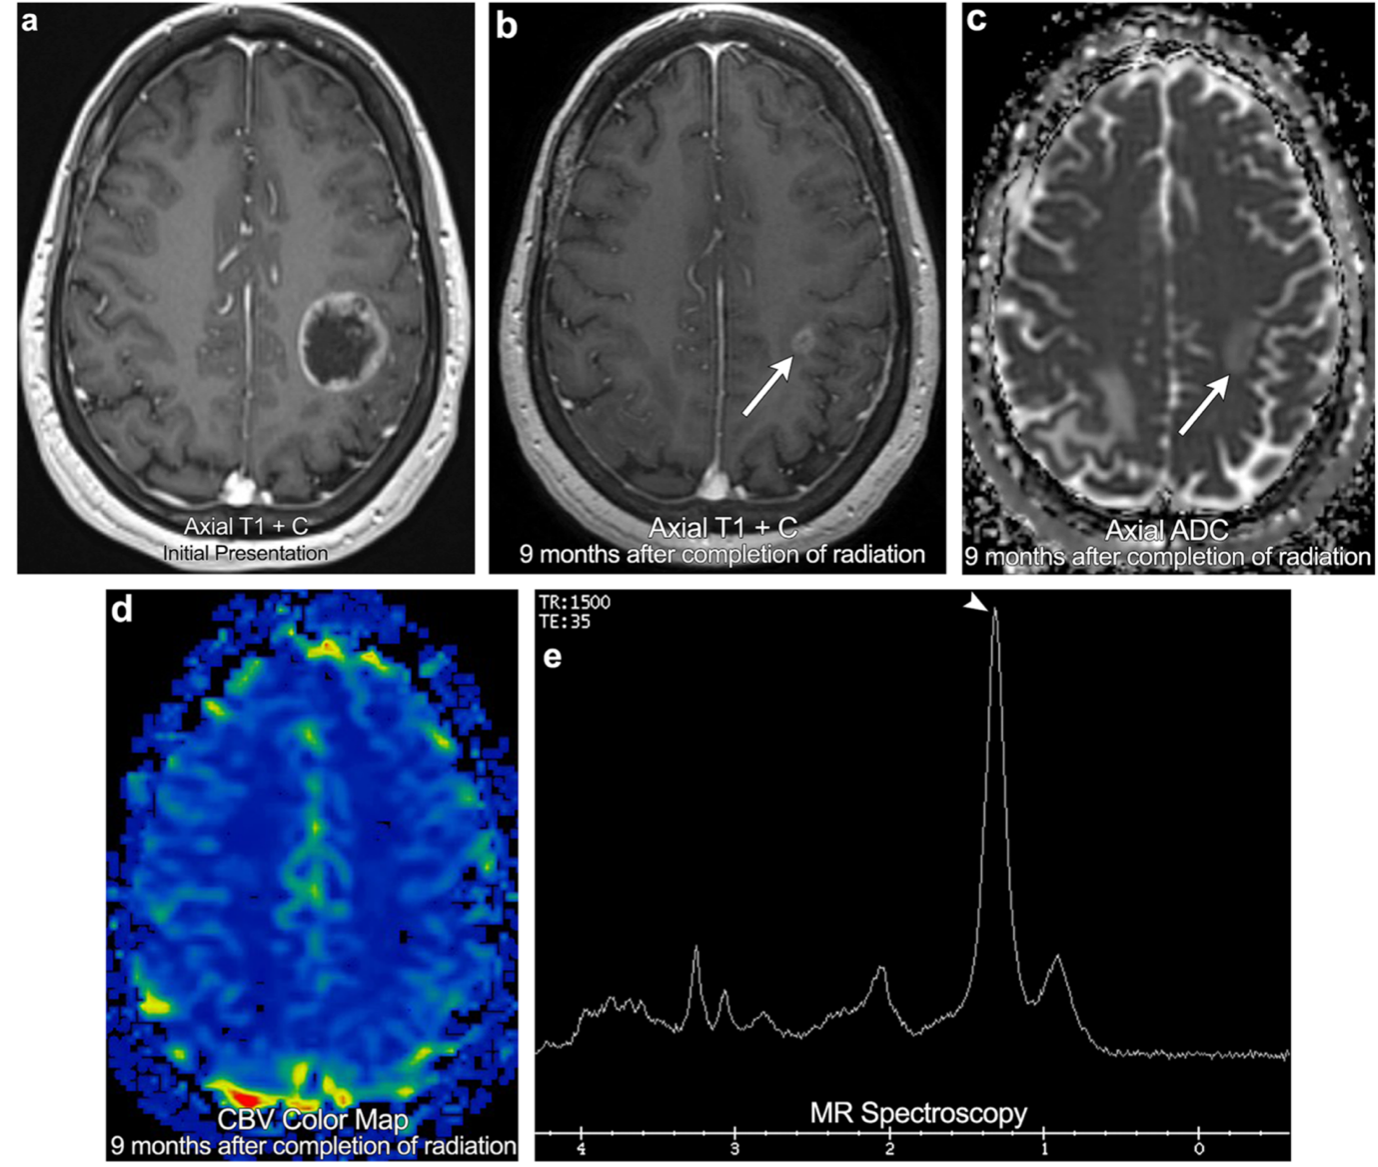

这些标准在很大水平上依赖于医学和放射影像学上的疾病进展,其定义是指病灶大小或出现任何新病灶>20%的增大。虽然中枢神经系统转移瘤现在开始被纳入...